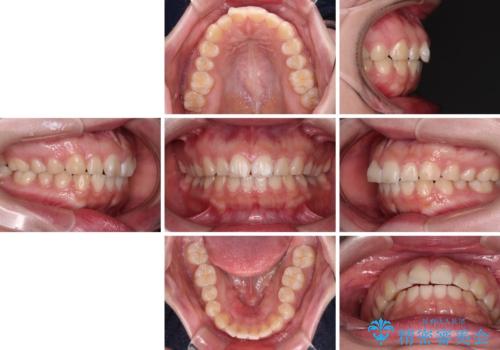

- 出っ歯と口の閉じにくさ、デコボコを気にして来院された患者様です。

口元の突出感を改善するため、上下左右第一小臼歯4本の抜歯を行い、ワイヤー装置による矯正治療を行うこととしました。

抜歯矯正を行ったことで、顎先のつっぱり感や口元の閉じにくさを解消することができました。